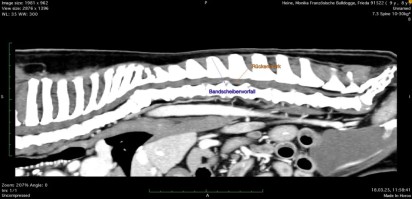

Auszug aus dem Artikel: Frieda wurde uns Mitte März mit Schmerzsymptomatik und einer gehfähigen Paraparese, also mit milden Ausfallserscheinungen der Hintergliedmaßen, vorgestellt. Die Symptome dieser Episode bestanden seit einigen Tagen akut. Die Computertomografie ergab Bandscheibenvorfälle mehrerer Bandscheiben, sowohl in der Hals- als auch in Brust- und Lendenwirbelsäule, so dass zur weiteren Abklärung, bei welchem Vorfall es sich um das akute Problem handelt, noch ein MRT angefertigt werden musste. Frieda hatte Glück – der auslösende Bandscheibenvorfall lag zwischen dem 1. und dem 2. Lendenwirbel und somit noch nicht im beschriebenen problematischeren Bereich. Frieda konnte erfolgreich operiert werden und das Rückenmark an dieser Stelle mittels Minihemilaminektomie und Fenestration entlastet werden. Bereits beim Fäden ziehen 10 Tage nach der Operation hatten sich die Symptome gebessert, diese Verbesserung hat sich bis zur Kontrolle 6 Wochen nach der Operation fortgesetzt.

Unsere Französische Bulldogge Frieda wurde im März 2025 in der AniCura Kleintierklinik Babenhausen untersucht, weil sie plötzlich Schwierigkeiten beim Laufen zeigte. Sie rutschte auf glatten Böden aus, zögerte beim Spazierengehen und kam nur schwer aus dem Sitzen hoch. Diese Symptome waren Anzeichen für Probleme an der Wirbelsäule. Zur genauen Diagnose wurde zunächst ein CT (Computertomografie) und anschließend ein MRT (Magnetresonanztomografie) durchgeführt. Dabei zeigte sich, dass Frieda unter mehreren Bandscheibenvorfällen an unterschiedlichen Stellen litt. Diese Bandscheiben waren teilweise stark verknöchert und wölbten sich in den Wirbelkanal vor, was Druck auf das Rückenmark ausübte. Zusätzlich wurden Verformungen an einigen Brustwirbeln und eine ausgeprägte Wirbelsäulenverkrümmung festgestellt.